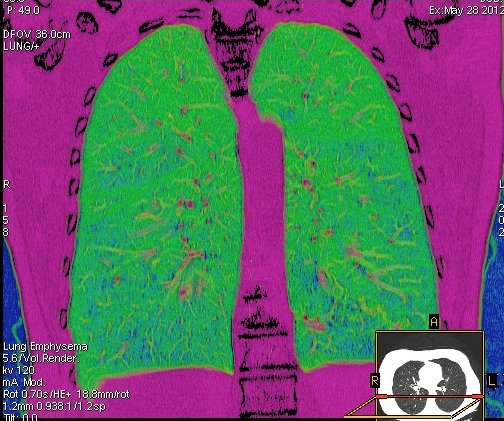

Foto: Aleksandar Ivković Foto: Aleksandar Ivković Foto: Aleksandar Ivković Strašna razlika kod pluća pušača i kovid pozitivne osobe autor: Božica Luković Zdravlje 23. jan. 2021. 12:06 > 23. jan. 2021. 12:15 0 Podeli vest: Radiolog Aleksandar Ivković od početka pandemije daje korisne informacije o svim aspektima kovida 19. On je nedavno uporedio rendgen snimke pluća zdrave osobe, pušača, osobe koja je zaražena gripom H1N1, a onda i osobe koja ima kovid 19. Razlike su zapanjujuće. Podeli vest: Oglas Objavu doktora Ivkovića sa njegovog bloga "Ljudi i ostale laži" prenosimo u celosti."Nedavno sam video u medijima da je neko preneo rdg sliku i razlike kod nalaza zdrave osobe, pušača i bolesnog od kovida 19. Kako nisam baš previše zadovoljan onim što je prikazano, evo kako to izgleda u našoj varijanti. Zdrava osoba CT nalaz kod zdrave osobe podrazumeva da ne postoje nikakvi poremećaji strukture plućnog parenhima, da su krvni sudovi uredni i da nema suženja disajnih puteva, kao i da nema uvećanih limfnih žlezda u hilusima pluća i medijastinumu. Foto: Aleksandar Ivković | Foto: Aleksandar Ivković * Foto: Aleksandar Ivković | Foto: Aleksandar Ivković Zdrava muška osoba mesec dana nakon zapaljenja pluća tokom kovida 19. Nalaz bez nekih posebnih problema iako se naziru tragovi zapaljenja. Snimak u boji je zdrava osoba, nepušač, bez ikakvih bolesti pluća u istoriji. Grip H1N1 Pokazaću samo drastične nalaze kod gripa H1N1, to je znači onaj grip koji je izazvao epidemiju španske groznice i epidemiju 2009. godine koja još uvek nije prestala (svake godine imamo makar 15%). Foto: Aleksandar Ivković | Foto: Aleksandar Ivković * Foto: Aleksandar Ivković | Foto: Aleksandar Ivković * Foto: Aleksandar Ivković | Foto: Aleksandar Ivković * Foto: Aleksandar Ivković | Foto: Aleksandar Ivković Nisu svi pacijenti imali ovakve nalaze, pokazujem one koji su imali tešku kliničku sliku. Kod gripa se sve odvija obično u sedam dana. Kao što se vidi, zapaljenje je bilo jednostrano, uglavnom. Ali kada je dolazilo do pogoršanja, onda je centralno obostrano dolazilo do edema pluća. Pušenje Kod pušača postoje razne varijante nalaza na plućima. U principu nisu tako dramatične kao što su zapaljenja. Nalaz na plućima kod pušača može biti potpuno normalan. Ovo ne pišem zato što podržavam pušenje, naprotiv, veliki sam protivnik, ali iznošenje laži nikada nije dobro. Dve dijagnoze su bitne kao posledica pušenja. Prva je hronična plućna opstruktivna bolest: Foto: Aleksandar Ivković | Foto: Aleksandar Ivković * Foto: Aleksandar Ivković | Foto: Aleksandar Ivković * Foto: Aleksandar Ivković | Foto: Aleksandar Ivković Jasna je razlika u nalazu, posebno na ovim slikama u boji, gde su ta plava polja delovi pluća koji su propali zbog cigareta (može da se uporedi sa zdravim plućima iznad).Druga bolest koja je česta kod pušača je u svakom slučaju karcinom. Foto: Aleksandar Ivković | Foto: Aleksandar Ivković * Foto: Aleksandar Ivković | Foto: Aleksandar Ivković * Foto: Aleksandar Ivković | Foto: Aleksandar Ivković * Foto: Aleksandar Ivković | Foto: Aleksandar Ivković Tkivo koje raste unutar pluća i razjeda ga. Takav je nalaz kod karcinoma pluća. Često je uzrok upotreba cigareta. Kovid 19 O kovidu sam pisao puno puta. Evo nekih slika, radi poređenja. Foto: Aleksandar Ivković | Foto: Aleksandar Ivković * Foto: Aleksandar Ivković | Foto: Aleksandar Ivković * Foto: Aleksandar Ivković | Foto: Aleksandar Ivković * Foto: Aleksandar Ivković | Foto: Aleksandar Ivković Nakon što pacijent bude izlečen od gripa ili kovida 19, pluća se mogu vratiti u normalu.To je razlika u odnosu na posledice upotrebe cigareta. Ovi snimci nisu postavljeni da bi se poredile bolesti, već da bi se ukazalo kako različite bolesti deluju na pluća. I ono što je veoma važno, ako neko dobije jednu od ovih bolesti, ne znači da u toku života neće dobiti drugu.Ne pišem zato smo smatram da sam najpametniji ili najpozvaniji da objašnjavam, nisam kao neki pojedinci ubeđen da samo ja imam znanje i istinu, pišem jer drugi ćute. Pišem jer ima i puno onih koji iznose laži, mora se tome stati na put.A ovi, koji pišu da sam umro, da sam oboleo od karcinoma, ovi koji mi žele da nađem dobro grobno mesto, šta da vam kažem, vi ste mi inspiracija. Svesni ste da sam u pravu i odlično znam da ste već uradili sve da se vakcinišete i mnogi od vas će to uraditi pre mene ali i dalje ćete ubeđivati druge da se ne vakcinišu i da je dobro za njih da se razbole i umru. Ima puno reči za vas u svim našim slovenskim jezicima, znate vi sami šta ste", piše dr Ivković.***Bonus video:https://youtu.be/MWucTT0qBsIPratite nas i na društvenim mrežama:FacebookTwitterInstagram Dr Lukić otkrio spisak svih antibiotika za kovid upalu pluća Zdravlje 0 Dr Žujović: Kako oporaviti pluća posle korone Zdravlje 0 Pet znakova da ti je kovid zahvatio pluća Zdravlje 0 Virusolog Ana Banko ruši veliku zabludu o ruskoj vakcini Emisije 0 aleksandar ivković korona kovid pluća snimak pluća Pratite nas na društvenim mrežama: Koje je tvoje mišljenje o ovoj temi? Učestvuj u diskusiji ili pročitaj komentare Budite prvi koji će ostaviti komentar Pošalji komentar Pročitaj komentare (0)